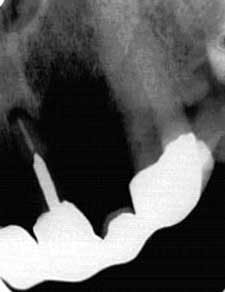

Plaintiff was a 45-year-old, telephone-company network technician who had been under the continuous care of his general dentist from 1975 until 1995. Plaintiff was compliant and diligent about his oral hygiene and followed all dental advice given by the dentist-defendant: i.e., when plaintiff was told he needed restorations, he had them done; when he was told he needed a root canal, he had it done; when he was told he needed a bridge, he had it done.

The plaintiff developed periodontal disease, which progressed until some of his teeth had no bony support. The plaintiff was never told about the onset or progression of periodontal disease until he visited a different dentist for a "second opinion," at which time he was told to "run, don't walk, to a periodontist." The plaintiff lost teeth and required four quadrants of periodontal surgery and expensive crown-and-bridge restorations.

The case settled during a mandatory pretrial mediation conference for $125,000.

The middle picture was taken one month after the patient's last visit to the defendant, at which time he was told he was "in fine shape."

(Used with permission from The Dentalaw Group, Boyd Shepherd, DDS, J.D., 16514 Canyon Chase Dr., Suite 200, Houston, Texas 77095)